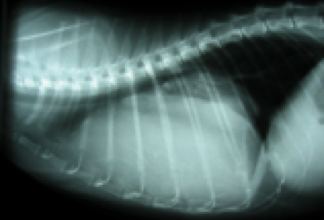

Das Röntgen

Bein Röntgenaufnahmen des Brustkorbes werden das Herz, die Lunge, die großen Blutgefäße, das Zwerchfell und Skelett dargestellt. Mit dieser Übersicht kann der Kardiologe eine Herz- oder Lungenerkrankung (z.B. Lungenödem – also Wasser in der Lunge, Stauungen der Blutgefäße), Lungenentzündungen, Tumore und eine Herzvergrößerung erkennen.

Herz eines gesunden Hundes in der seitlichen Aufnahme